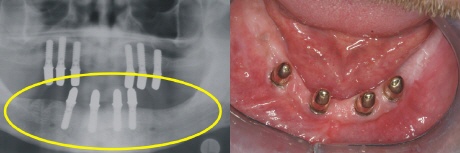

Der zahnlose Unterkiefer rechts im Bild bietet keinen Halt mehr für eine Prothese. Links zeigt sich der zahnlose Knochenabschnitt im Röntgenbild (gelber Kreis).

Im Unterkiefer können die vier Implantate (Standardversorgung) im vorderen Kieferbereich eingebracht werden (gelber Kreis im Röntgenbild).